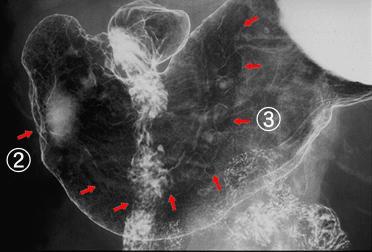

Early gastric malignant lymphoma with pyloric stenosis

Tokyo Pref., Cooperative study between National Cancer Center and Kyushu Cancer Center

Malignant Lymphoma/Malignant lymphoma

Stomach/More than one of above

X-ray

40 -

submucosa